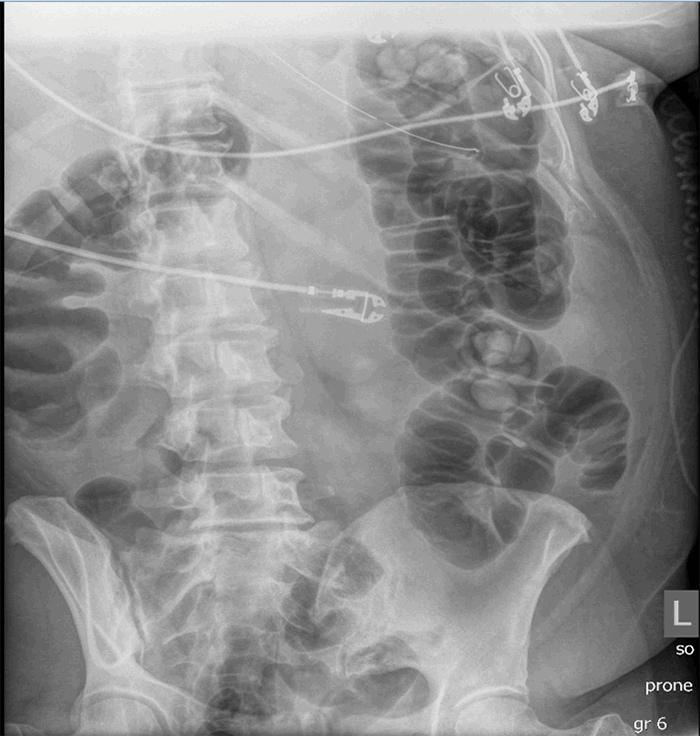

The patient was admitted to the telemetry floor and started on hydroxychloroquine, atorvastatin, and azithromycin. Her oxygen requirement continued to increase, and she was transferred to the ICU due to refractory hypoxemia and subsequently intubated within 24 hours of admission. On hospital day four, she was noted to have increased abdominal distension with an abdominal X ray showing predominantly diffuse colonic dilatation (Figure 3a). WBC count and lactate were both normal. She was started on an aggressive bowel regimen and a rectal tube was placed. By the next day, there was a slight improvement in her colonic dilatation (Figure 3b), and by hospital day six, her colonic distension was completely resolved (Figure 3c). Neostigmine was not used.

Figure 3. Case 3 CT imaging (a) abdominal X-ray showing predominantly diffuse colonic dilatation; (b) abdominal X-ray showing slight improvement in colonic dilatation; (c) abdominal X-ray showing complete resolution of colonic distension